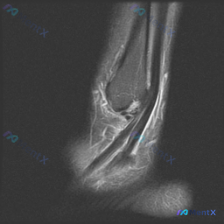

最近看到这个踝关节MRI病例,原始观察提示有软组织积液,整理一下完整的影像信息和分析思路给大家讨论。

这是一张踝关节跟骨区域的矢状位T2加权脂肪抑制(或STIR)序列MRI,液体/水肿呈现高信号,脂肪信号被抑制,方便观察软组织病灶。

- 骨骼结构:跟骨后上部及结节部可见大范围高信号,提示骨髓水肿,骨皮质轮廓没有断裂;距骨和胫骨远端形态信号都正常。

- 肌腱韧带:跟腱远端止点局部增厚,信号不均匀,止点周围软组织有弥漫性高信号(水肿渗出)。

- 软组织:跟骨后方皮下组织、跟腱周围深部软组织、Kager脂肪垫区域都可见弥漫肿胀和高信号,提示炎性反应。

- 关节:踝关节间隙正常,没有明显关节面缺损。